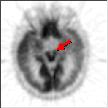

Click on image above to view full-size image.

The first step in analyzing image quality is to look for artifacts. For example, this scan is too noisy.